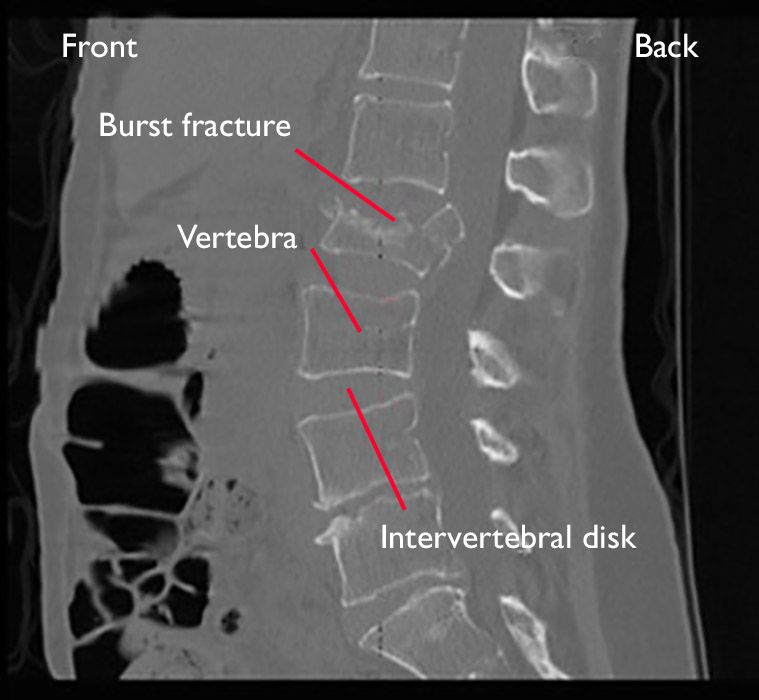

A transverse process fracture happens when there is a break in a portion of one of the bones that make up the spine.

Fracture-dislocations of the thoracic and lumbar spine are caused by very high-energy trauma. The pieces may be held in place with screws or other medical hardware. Transverse process fractures can be treated quickly and effectively with the recommended protocol after excluding any accompanying organ injuries or other spinal injuries. These protrusions allow muscles and. 3 or less thoracolumbar transverse process fractures ITPFs without any other spinal column fracture or neurologic deficit identified by CT scan during the routine trauma work-up do not require consultation of the spine service. A high index of suspicion for other injuries should be maintained. A transverse fracture occurs when a bone has broken perpendicular to its the length. There are two transverse processes in a vertebral bone. Orthotic management with a McCausland chairback or Taylor orthosis limiting hyperextension is usually required for the spinous process fracture.

These breaks are usually very serious and must be treated by a doctor to ensure proper healing. It is argued that when the force required to break a transverse process is big enough then an internal organ will be in the cases also damaged by it. This fractured or broken portion is known as the transverse process and it is the part of the spinal column that shoots out like a wing. Transverse process fractures are associated with other spinal non-transverse process fractures and non-spinal injuries solid organ injury pelvis fractures etc. How is a transverse process fracture treated. Managing there is a process fracture essentially a conservative and sign- driven process. There are two transverse processes in a vertebral bone.